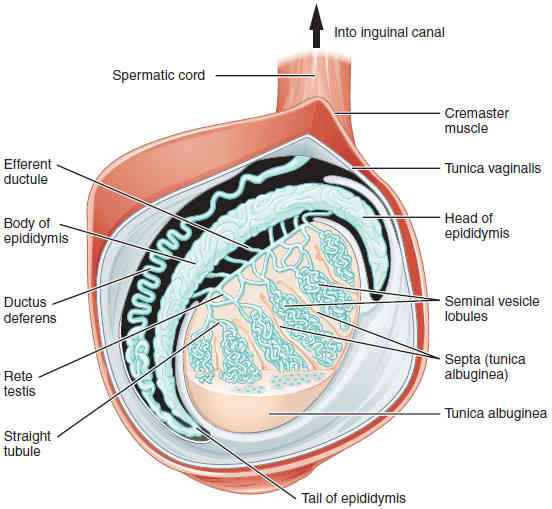

This page is under construction. For now, it is just a resource of the images found in the OpenStax Anatomy and Physiology Handbook. It wil slowly change into a revision tool. Each slide has a number. Use this to refer to the slide. When completed, it will have an unlabelled section, with labelled slides in parallel. On the unlabelled slides, write your answer and use the labelled slide to assess yourself. Keep track by also noting the number on each slide. Improvement at each attempt is important, more so than full marks on a first attempt.